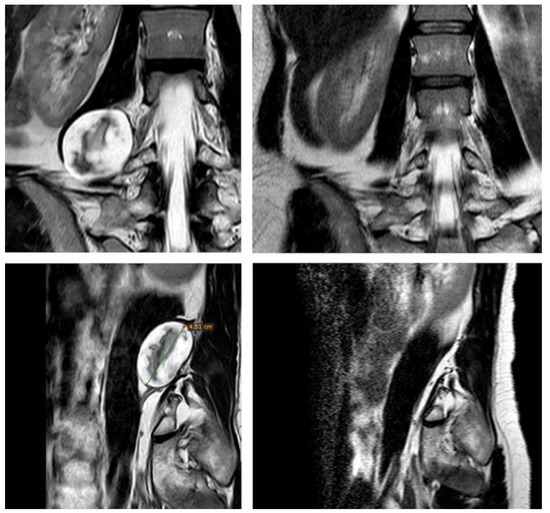

Giant Atypical Neurofibroma of the Calf in Neurofibromatosis Type 1: Case Report and Literature Review

Background and Clinical Significance: Neurofibromatosis type 1 (NF1) predisposes individuals to various peripheral nerve sheath tumors (PNSTs), including benign neurofibromas, malignant peripheral nerve sheath tumors (MPNSTs), and intermediate lesions known as atypical neurofibromatous neoplasms of uncertain biologic potential (ANNUBP), previously often termed atypical neurofibroma. These atypical lesions are considered premalignant precursors to MPNST. Case Presentation: We present the case of a 33-year-old male with NF1 who developed a rapidly growing, painful mass in his right calf. Clinical examination revealed signs consistent with NF1. Magnetic resonance imaging showed a large, heterogeneous mass in the lateral compartment. Biopsy revealed a neurofibroma with hypercellularity, moderate atypia, scarce S100 positivity, focal CD34 positivity, and an elevated Ki-67 proliferation index of 10–12%, consistent with ANNUBP. The patient underwent wide surgical resection, including the fibula and peroneal muscles. At the 30-month follow-up, there was no local recurrence, though the patient had a mild residual limp. Discussion: This case highlights the clinical presentation, diagnostic features, and management considerations for ANNUBP in NF1, emphasizing the importance of recognizing warning signs and the role of pathology in guiding treatment for these high-risk precursor lesions. Full article